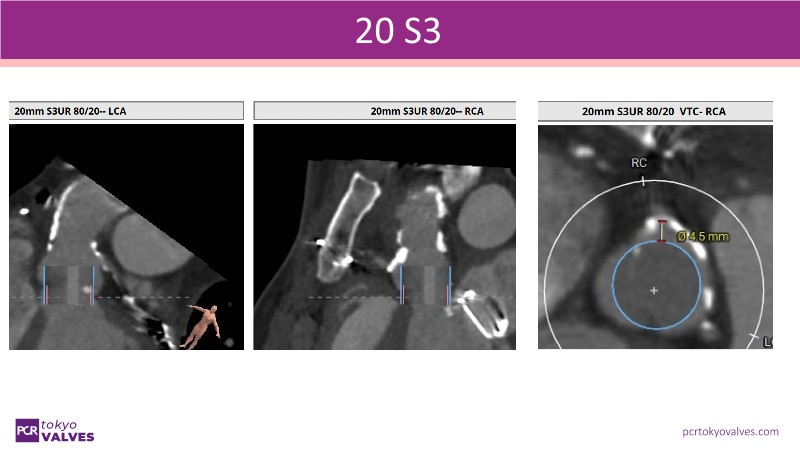

In this expert-led session, explore new frontiers in TAVI, focusing on bicuspid aortic valves, small annulus, and the risk of secondary interventions. Gain insights from the latest randomized trials (RHEIA) and registry data (CAvEAT), with real-world case discussions highlighting their clinical impact.

- To discuss the new frontiers in TAVI including the treatment of patients with bicuspid aortic valve, small annulus and risk of secondary intervention

- To discover the results of latest randomised clinical trials (RHEIA) and registry data (CAvEAT) in these TAVI subsets

- To understand the clinical impact of these data sets through case presentations